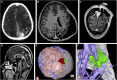

Objective: To describe a case series showing the application of immersive VR involving both "top-down" from skull to lesion and "bottom-up" from lesion to skull approaches for trajectory planning in pediatric neurosurgical patients.

Methods: We detail the preoperative and intraoperative application of VR and clinical courses of 5 children (aged 7-14 years) with anatomically challenging intraparenchymal lesions that posed operative risks to nearby vascular anatomy and fiber tracts. Preoperative planning consisted of standard presurgical evaluation with computed tomography and magnetic resonance imaging used to render 3-dimensional models that could be viewed and manipulated using desktop software and immersive VR headsets and hand controllers by the surgeon and family. Patient satisfaction was evaluated by survey. Surgical outcomes were degree of seizure control or extent of resection.

Results: Three patients underwent lesion resection and 2 laser ablation. Modifications to 2-dimensional and "top-down" VR trajectory plans were made after "bottom-up" navigation in all cases. All families reported that the VR enhanced their understanding of the procedure. There were no complications, and no patients suffered permanent neurological deficits postoperatively. Gross total resection was achieved in all lesional cases, and patients with epilepsy achieved seizure freedom at 2 years postoperatively.

Conclusion: Immersive VR allows operative corridors to be virtually traveled and viewed from a "top-down" and "bottom-up" perspective, as if looking up from under a forest canopy of overlying anatomy, for optimal trajectory planning and improvement of family understanding in pediatric neurosurgery.